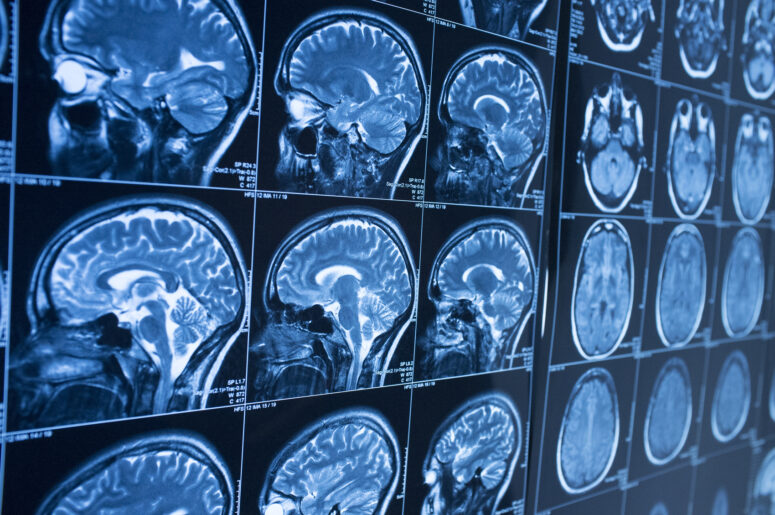

BrainLine also comments on the severity of a TBI and the impact such an injury can have on an individual’s life. Regardless of whether it is a moderate or severe TBI, BrainLine points out that polytrauma often goes hand-in-hand with TBI, and that many patients must deal with multiple disabilities brought on by the initial accident. Basic motor skills can also become an obstacle, such as difficulty thinking, vision problems, struggles with social relationships and other challenges. BrainLine lists difficulty sleeping, physical paralysis and memory problems as other potential effects. An accident involving the head can quickly become the most frightening moment in a person’s life, but various resources and the help of professionals can help victims make the process more manageable.